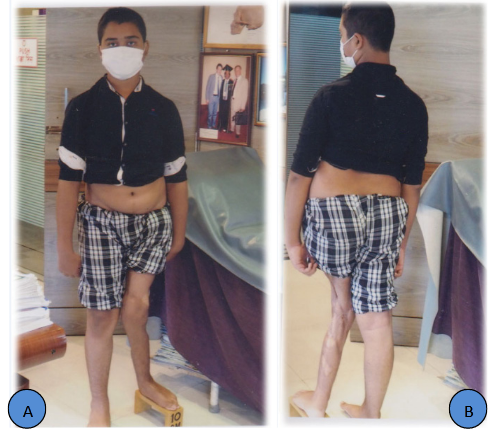

A 14 years old boy sustained motor vehicle injury in the left inferior extremity at the age of 8. He was treated at Combined Military Hospital, Dhaka at that time because father is an Army personnel. Now, he was referred to Bari-Ilizarov Orthopaedic Centre for further management, that is for correction of deformity and L. L. D. Plain X-ray and clinical ndings showed his left lower extremity with distal femur valgus deformity, proximal tibia valgus and procurvatum deformity. He was complaining left knee pain and his gait was awkward. His father was anxious regarding his deformity correction and lengthening of left lower limb.1–5

Figure 1 A-J 14 years old boy, Post Traumatic Genu Valgum with Valgus Deformity of left Lower Femur and Upper Tibia Valgus and Procurvatum Deformity with 10cm L. L. D and Puckering of Skin around Knee with Bad Scar.